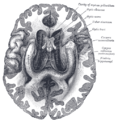

| Inferior view of the human brain, with the cranial nerves labelled. | |

العصب البصري يتألف من محاور عقد عصبية للشبكية وخلايا Portort. وهو يترك المدار (العين) عبر القناة البصرية ،بشكل postero-medially تجاه chiasm البصرية حيث يوجد partial decussation من الألياف من حقول البصرية للأنف من كلتا العينين. معظم المحور العصبية للعصب البصري تنتهي في lateral geniculate nucleus حيث المعلومات تنتقل إلى القشرة البصرية، في حين أن المحاور العصبية الأخرى تنتهي في الـ pretectal nucleus وتشارك في حركات العين الانعكاسية ومحاور عصبية أخرى تنتهي في suprachiasmatic nucleus وتتدخل في تنظيم دورة النوم واليقظة. ويزيد قطرها حوالي 1.6 ملم من داخل العين، إلى 3.5 ملم في المدار إلى 4.5 ملم داخل فضاء الجمجمة. وأطوال مكونات العصب البصري 24 ملم في المدار، 9 ملم في القناة البصرية و 16 مم في فضاء الجمجمة قبل أن ينضم إلى chiasm البصرية. هناك ،يحدث الـ decussation الجزئي وحوالي 53 ٪ من الألياف تتشابك لتكون الـ optic tracts. معظم هذه الألياف تنتهي في جسم geniculate الأفقي.[2]